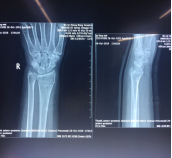

手法整复桡骨远端骨折、踝关节骨折、尺骨骨折、掌骨骨折、指骨骨折、跖骨骨折及肩关节脱位、桡骨小头半脱位等各类骨折脱位十余例,行小夹板固定及石膏托外固定十余例。